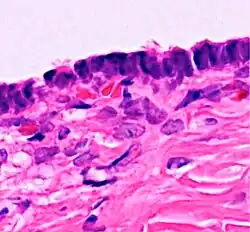

| Cystadenoma | Serous cystadenoma | Cyst lining consisting of a simple epithelium, whose cells may be either:[26]

|